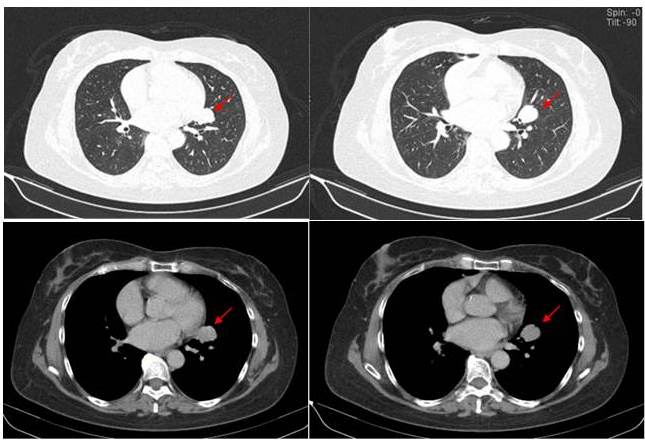

Se trata de paciente femenina de 59 años de edad, con antecedente de terapia supresora a base de anti - TNF y metrotexate debido a artritis reumatoide, quien refiere inicio de su enfermedad actual en marzo de 2010 cuando comienza a presentar tos seca de inicio insidioso, concomitantemente dificultad respiratoria progresiva motivo por el cual acude a centro de salud donde indican tratamiento médico presentando mejoría. La paciente acude a su consulta de reumatología para su control y seguimiento por el uso de la terapia anti-TNF, para su seguimiento se le realiza evaluación médica completa, la cuál incluye examen físico, exámenes de laboratorio y radiografía del tórax (proyección póstero-anterior). La exploración física fue normal y en la radiografía de tórax póstero-anterior, se descubrió una imagen para-cardíaca izquierda a nivel del parénquima pulmonar tipo nodular densa ovalada de borde bien definidos que mide aproximadamente 3,0 cm x 1,7 cm sin calcificaciones u otras anomalías (Figura 1). Se realizó una tomografía computarizada de tórax de alta resolución con contraste intravenoso que reveló una lesión nodular ovalada, homogénea de 26 mm, adyacente al hilio pulmonar izquierdo, borde bien definidos. Resto del parénquima pulmonar sin lesiones focales, estructuras adyacentes conservadas (Figura 2). Debido a los efectos inmunosupresores de la terapia anti-TNF, debe descartarse la posibilidad de infección por mycobacterium tuberculosis (TBC). Se practican exámenes de hemograma, química sanguínea cuyos reportes fueron normales, al igual que las espirometría y la bronco-fibroscopia. El test de la tuberculina PPD, tres baciloscopias y tres citologías de esputo fueron negativas, así como el bronco-aspirado selectivo realizado durante la bronco-fibroscopia y las determinaciones del VIH, Ca 19,9, Ca 125, alfafetoproteína y antígeno carcinoembrionario (CEA).

Debido al hallazgo de la radiografía se decide llevar a cabo un procedimiento de toracentesis diagnóstica, la cual fue positiva para líquido pleural serohemático, extrayéndose 20 cm3 para su estudio citoquímico y citológico. El resultado de la citoquímico de dicho líquido se reporta como un exudado con una celularidad a predomino de células tipos linfocitos 73 %, se programa y se realiza biopsia pleural con aguja de Abrams más colocación de sonda torácica conectada, drenaje posterior a control radiológico se observa imagen de masa posible lesión tumoral que ocupa lóbulo inferior del pulmón derecho. Se realizó una tomografía computarizada de tórax de alta resolución con contraste intravenoso que reveló una lesión redondeada, homogénea de 33 mm x13,7 mm, que ocupa la base del pulmón derecho (Figura 6).